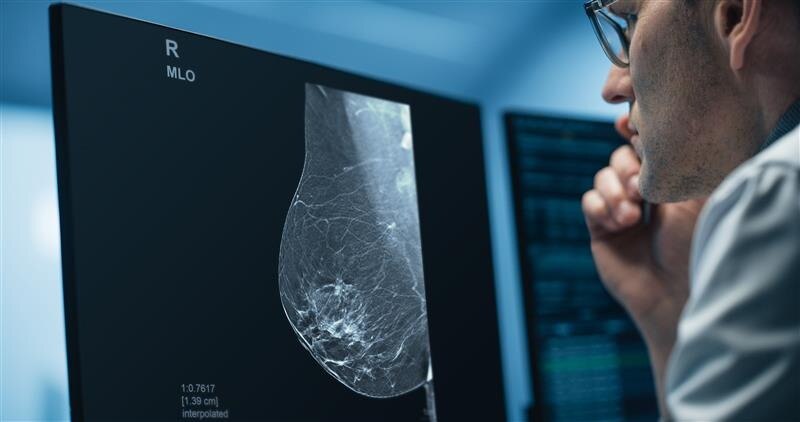

Pristina Via

Download

Pristina Recon DL

GEHC announced that it has received FDA Premarket Authorization for Pristina Recon DL.

Nov 26, 2025